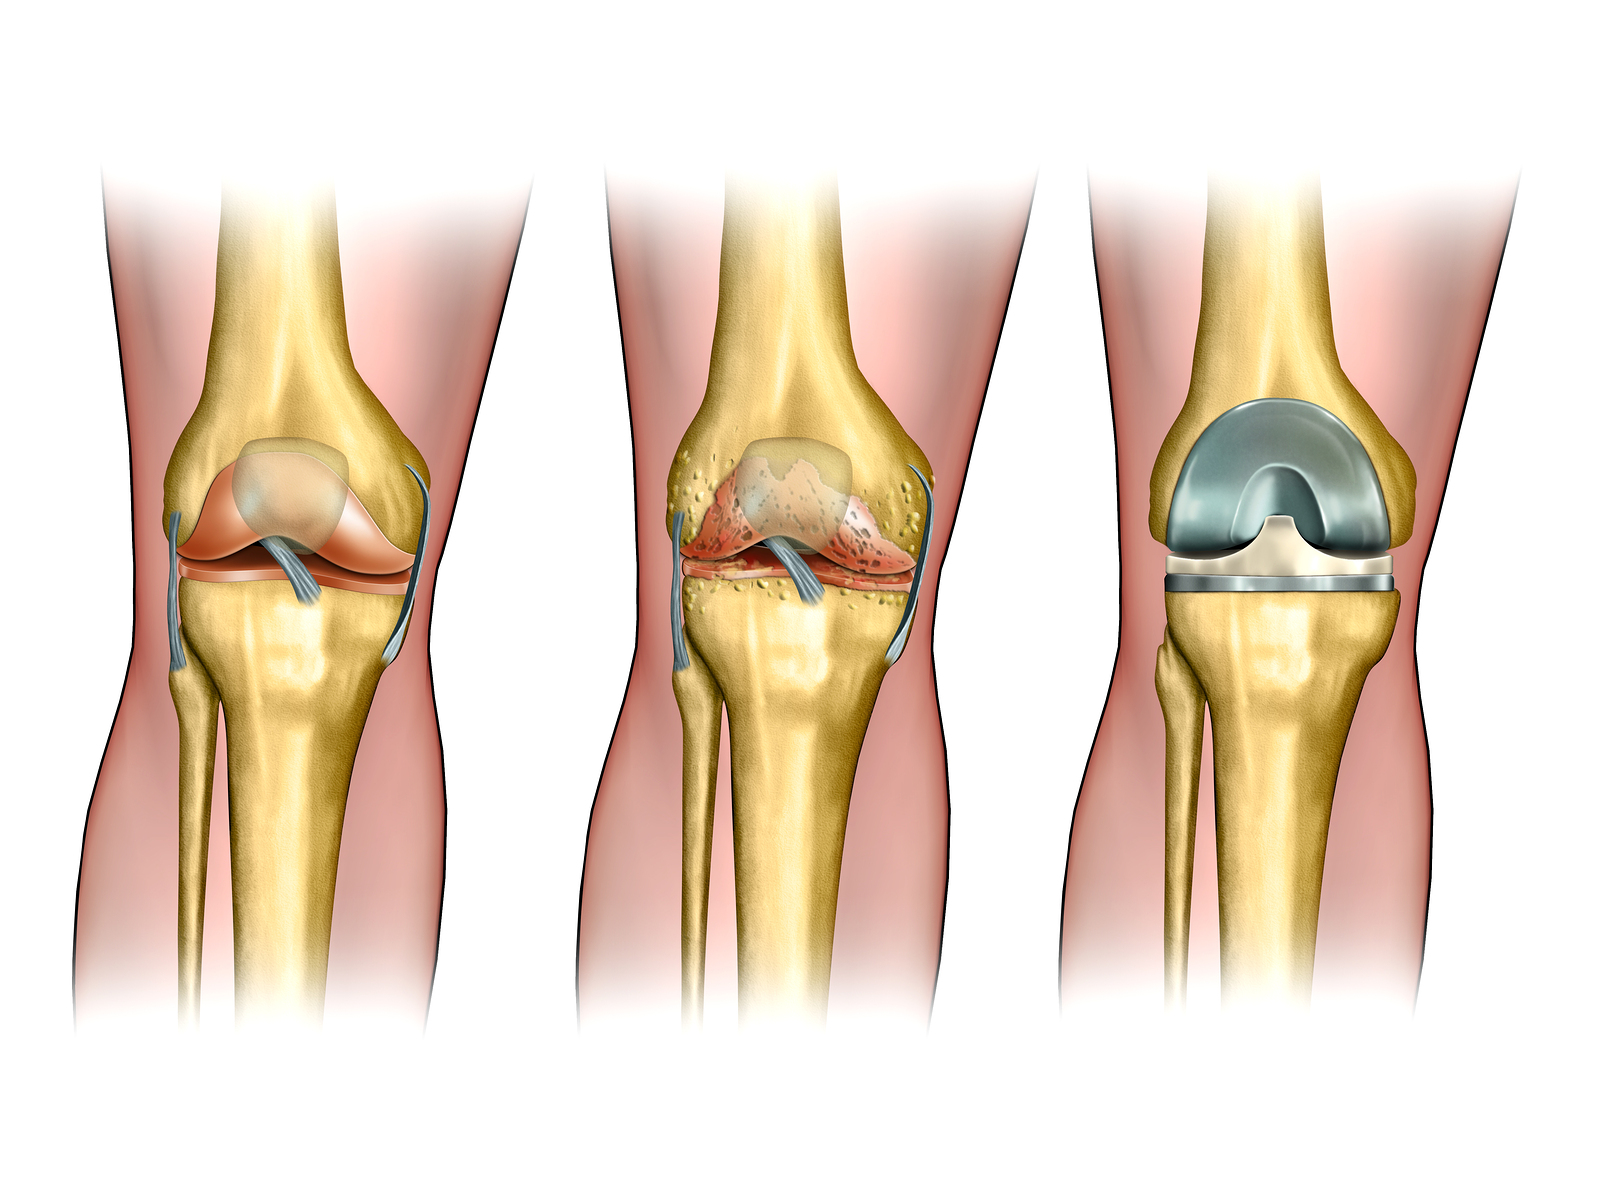

Knee replacement surgery — also known as knee arthroplasty (ARTH-row-plas-tee) — can help relieve pain and restore function in severely diseased knee joints. During knee replacement, a surgeon cuts away damaged bone and cartilage from your thighbone, shinbone and kneecap and replaces it with an artificial joint made of metal alloys, high-grade plastics and polymers.

Knee replacement surgery (arthroplasty) involves replacing a damaged, worn or diseased knee with an artificial joint.

There are two main types of surgery, depending on the condition of the knee:

1. total knee replacement (TKR) – both sides of your knee joint are replaced

2. partial (half) knee replacement (PKR) – only one side of your joint is replaced in a smaller operation with a shorter hospital stay and recovery period

The most common reason for knee replacement surgery is osteoarthritis. Other conditions that cause knee damage include: